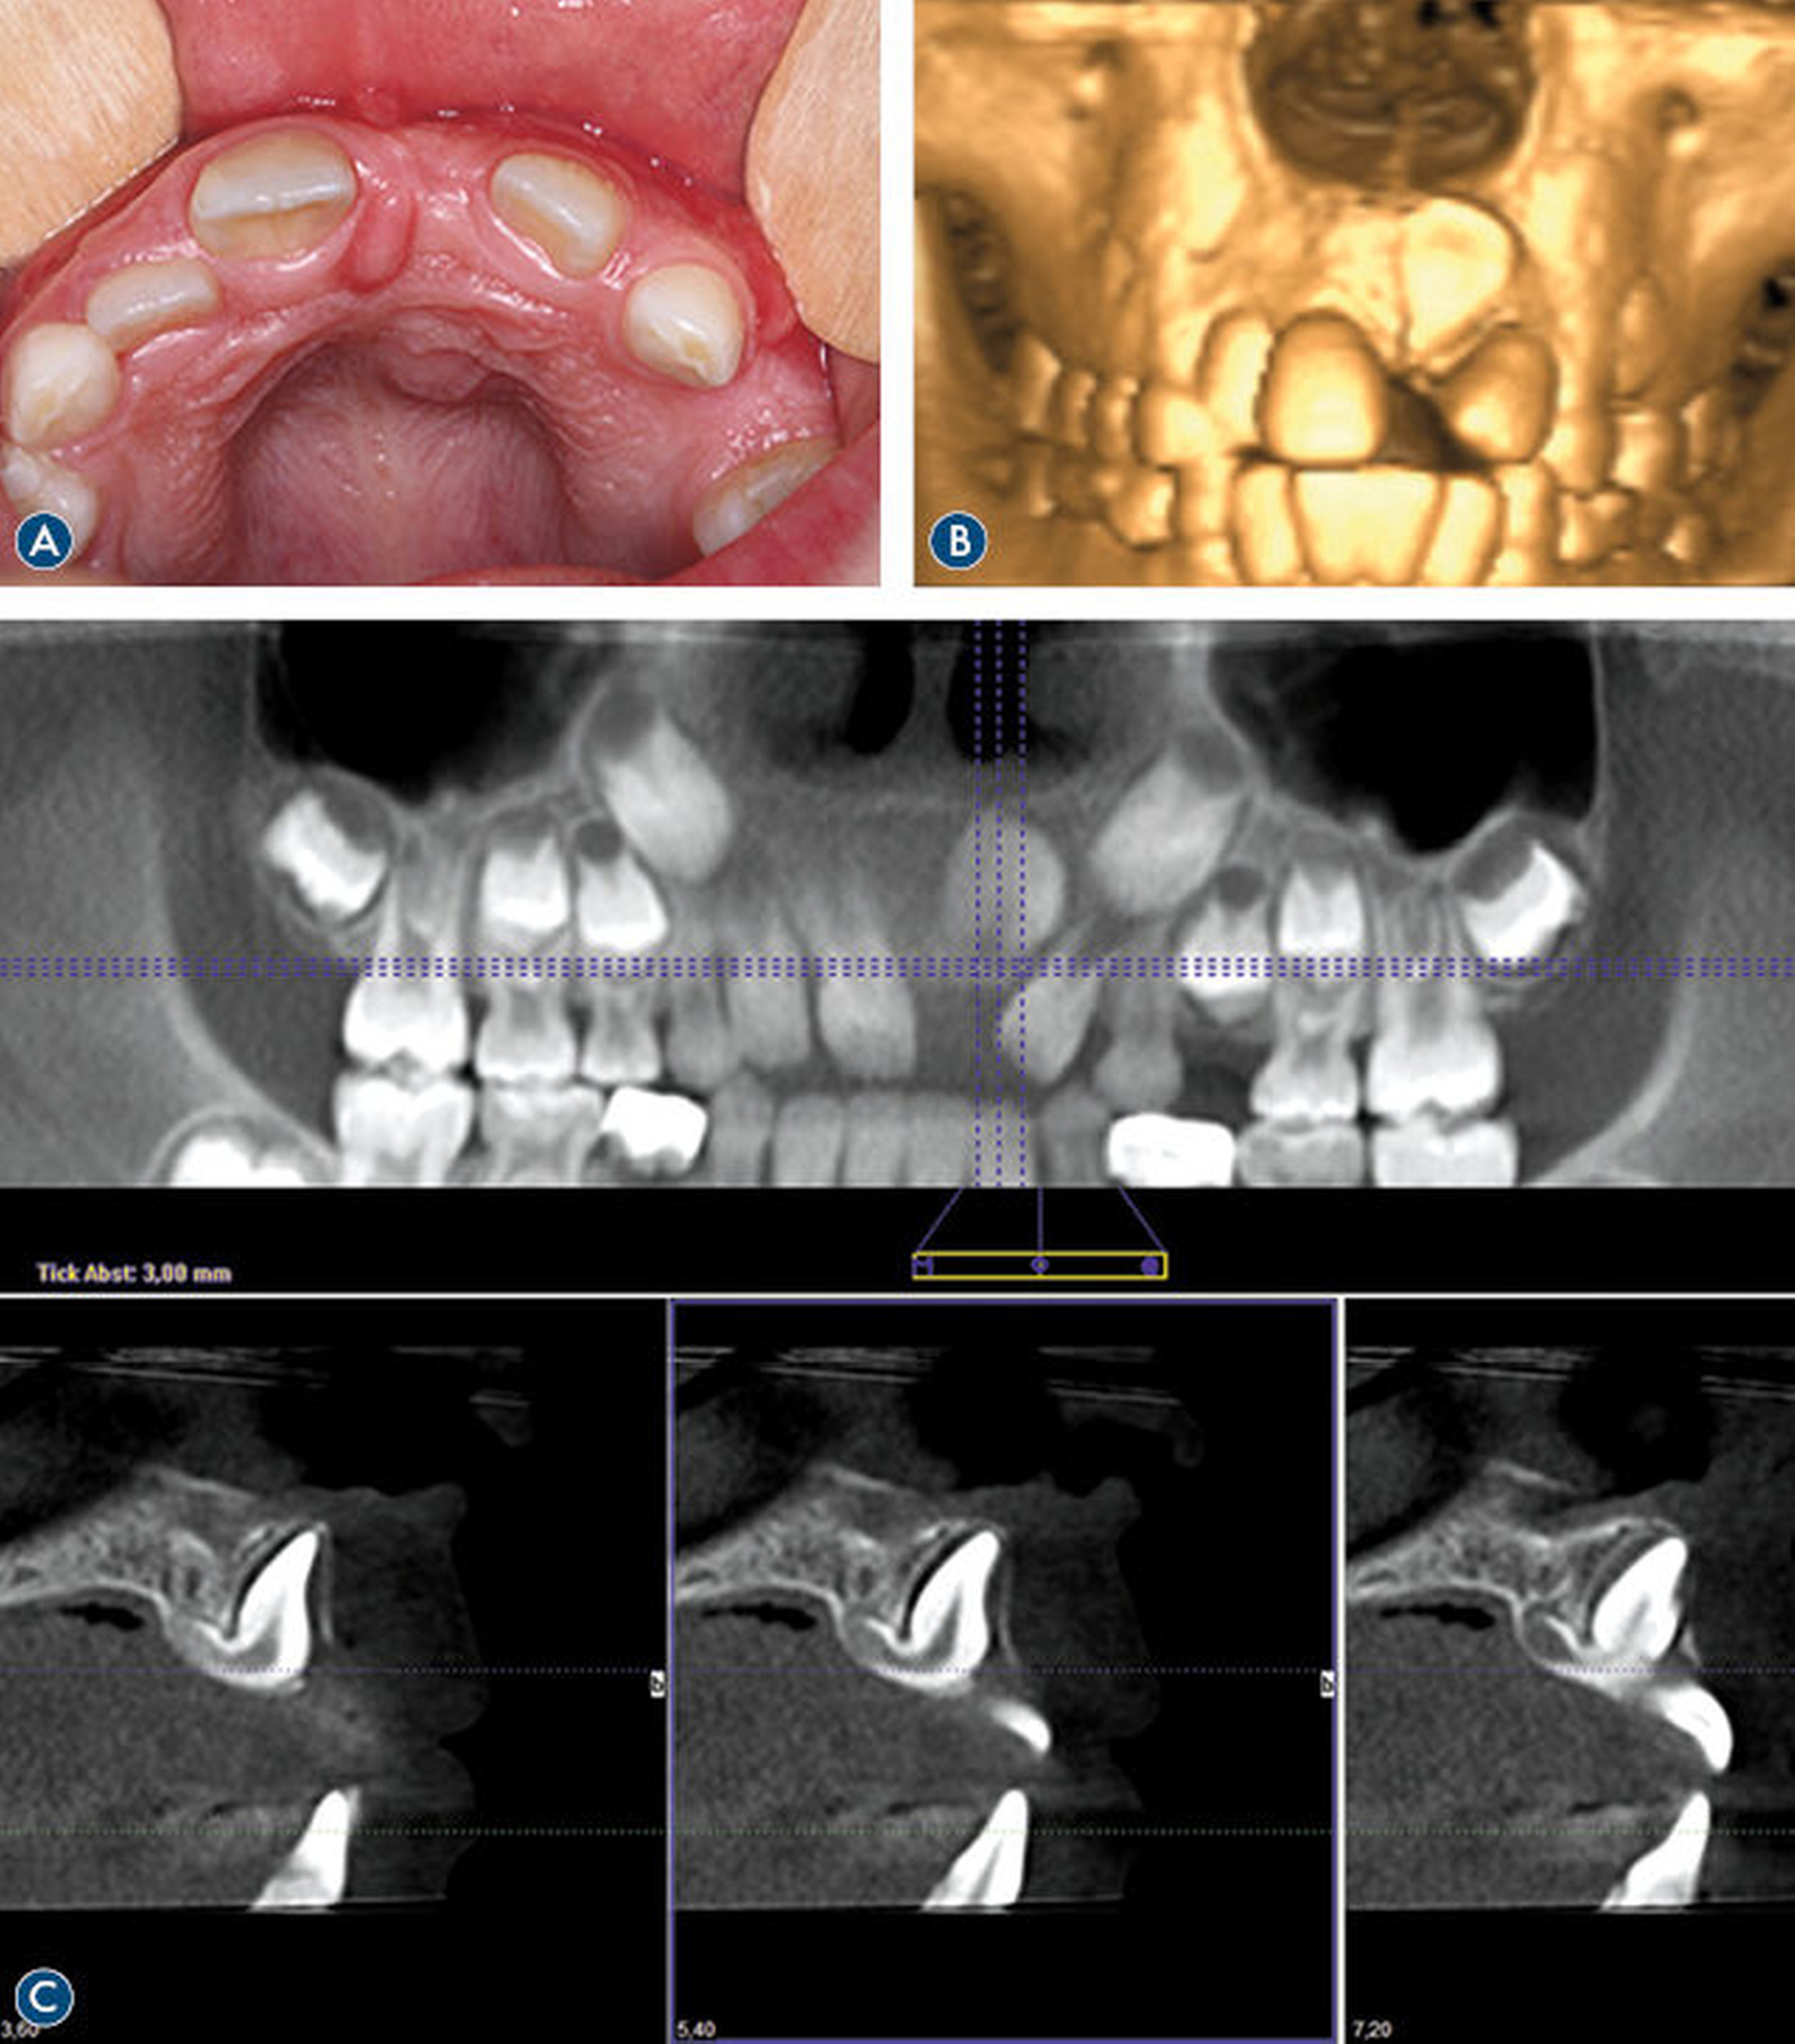

Im Einzelfall können zusätzlich dreidimensionale Röntgenverfahren zur Anwendung kommen, wenn therapeutisch relevante Informationen aufgrund von Anamnese oder Befund dringend benötigt werden (Abbildung 4). Allerdings muss bei Kindern diese Entscheidung kritisch abgewogen werden, da deren Gewebe deutlich empfindlicher auf die Wirkungen ionisierender Strahlung reagieren. Kinder unter zehn Jahren haben eine dreifach höhere Wahrscheinlichkeit für strahleninduzierte stochastische Effekte als 30-Jährige [Horner et al., 2004].

Im Unterschied zum DVT (Digitale Volumentomografie) erlaubt das CT (Computertomografie) neben der beiden Verfahren gemeinsamen Darstellung von Kiefer-/Gelenkfrakturen und dislozierten Zähnen oder Zahnfragmenten zusätzlich die Detektion und Lokalisation von Fremdkörpern im Weichgewebe sowie die weiterführende Diagnostik bei Verdacht auf das Vorliegen von Schädel-Hirn-Verletzungen. Bei vorliegender Indikation sollte das DVT dem Standard-CT aufgrundder niedrigeren Strahlenbelastung vorgezogen werden (Empfehlung 5).